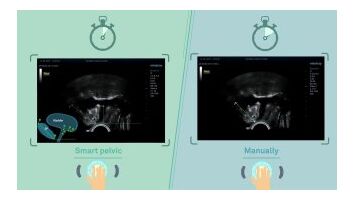

Smart Pelvic - новое решение, позволяющее значительно упростить диагностическую процедуру и свести к минимуму время исследования функций мышц тазового дна. Благодаря чрезвычайно простому пользовательскому интерфейсу, программа генерирует стандартную систему координат и автоматически просчитывает все связанные измерения в течение нескольких секунд.